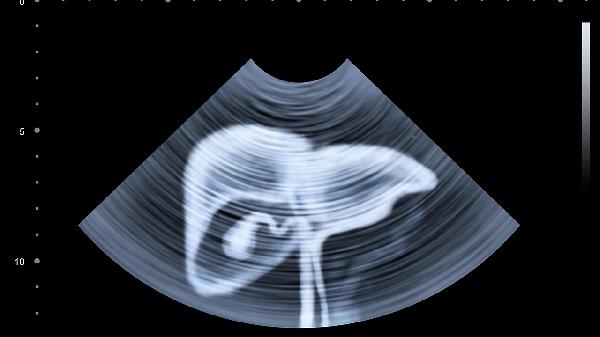

通过明确肝脏硬度值可以用于评估是否存在肝硬化、肝纤维化等。一般认为肝脏硬度的正常值在2.8kPa~7.4kPa,如果此项数值超过了9.5kPa,通常表示肝脏出现了比较严重的纤维化,应积极配合医生治疗,否则有可能会导致疾病加重,危害生命健康。